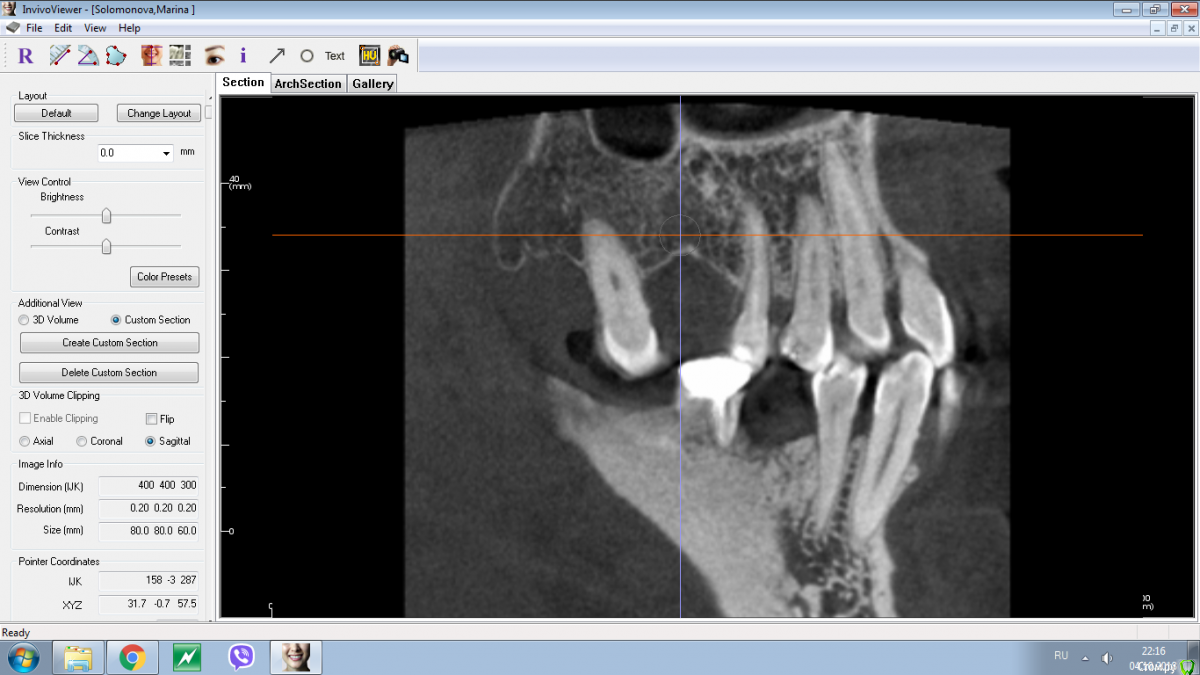

Nazim_NV86 Опубликовано 4 октября, 2018 Поделиться Опубликовано 4 октября, 2018 А как Вы проверяете интеграцию?На ощупь и на глаз )) Если заглушка покрыта хоть немного костью, этого факта достаточно. Если при выкручивании её прилагаются усилия. Ключ никогда не использую. По поводу подождать или перекрутить не могу однозначно сказать. КТ бы. Я бы не стал спустя 4 месяца ещё надеятся раз вы говорите что ставили не в графт. Ссылка на комментарий

Nazim_NV86 Опубликовано 4 октября, 2018 Поделиться Опубликовано 4 октября, 2018 Проверяйте кость на наличие остатков пломбировочных материалов или другой ятрогении. Ссылка на комментарий

Nazim_NV86 Опубликовано 4 октября, 2018 Поделиться Опубликовано 4 октября, 2018 А что в области 1.7 ?? Это губка... альвожиль ?? Ссылка на комментарий

Shakirbura Опубликовано 4 октября, 2018 Автор Поделиться Опубликовано 4 октября, 2018 А что в области 1.7 ?? Это губка... альвожиль ??Альвостаз. Ссылка на комментарий

Shakirbura Опубликовано 4 октября, 2018 Автор Поделиться Опубликовано 4 октября, 2018 (изменено) Срез КТ до операции.Здесь наверное можно придраться, не? Изменено 4 октября, 2018 пользователем Shakirbura Ссылка на комментарий